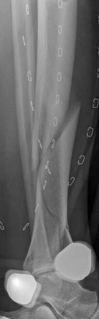

The management of complex tibial shaft fractures with extension into the distal articular surface (the tibial plafond or pilon) represents one of the most formidable challenges in orthopedic traumatology. These injuries typically result from high-energy mechanisms, such as a fall from a significant height or a motor vehicle collision, where axial loading forces are combined with severe rotational and shear vectors. The classic presentation, as highlighted in our index case of a 26-year-old male who fell 3 meters into a hole, involves not only catastrophic bony disruption but also devastating injury to the surrounding soft tissue envelope. The delicate nature of the soft tissues in the distal third of the leg, characterized by sparse muscular coverage and a precarious vascular supply, dictates the entire trajectory of clinical decision-making.

Initial management in these high-velocity scenarios mandates the application of a spanning external fixator to achieve skeletal traction, restore length, and allow the soft tissue envelope to recover. This temporary stabilization minimizes ongoing secondary soft tissue trauma from mobile fracture fragments. However, the application of external fixators is not without risk; meticulous pin placement is required. For instance, calcaneal transfixion pins must be placed with strict attention to the neurovascular bundle to avoid iatrogenic tibial nerve irritation, an issue that required revision in the early phase of our index patient's care.